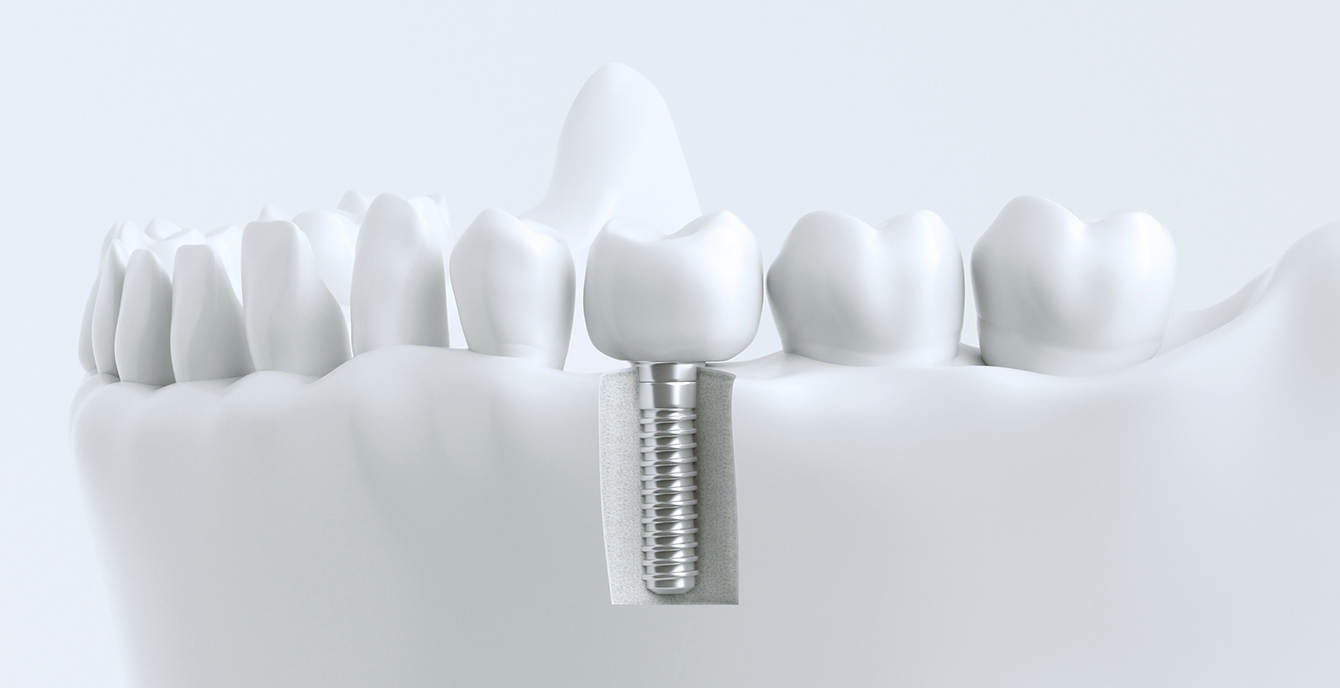

当院のインプラントは、40年以上の歴史があるノーベルバイオケア社(スイス)を使用しており、骨との親和性に優れる「純チタン」の表面に「タイユナイト」と呼ばれる表面加工が施されており、周囲の骨形成が促進されると言われています。